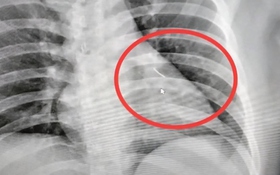

Mổ bụng cứu chó hoang, bác sĩ “đứng hình” khi phát hiện dây chuyền vàng đắt đỏ

Cộng đồng mạng Thứ 7, 23/05/2026 | 00:30

Một ca mổ tưởng chừng chỉ để cứu chiếc chân gãy của chú chó hoang bất ngờ hé lộ bí ẩn khó tin khi các bác sĩ phát hiện một sợi dây chuyền vàng đắt đỏ nằm sâu trong cơ thể nó. Biết nguyên nhân ai cũng gật gù.